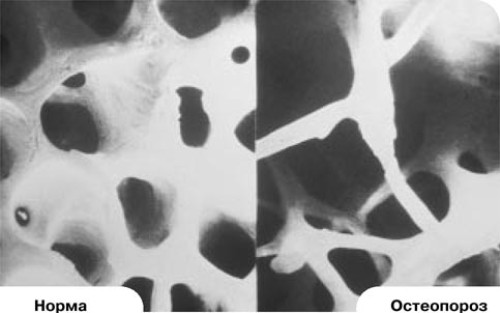

Остеопороз костей – постепенное, но стойкое разрежение костной ткани, что приводит к уменьшению прочности костей и повышению рисков переломов. Увеличивают риск развития остеопороза следующие факторы:

Во многом обеспечение организма кальцием зависит от поступления его из пищи, а для нормального его усвоения в рацион следует добавлять витамин D. После 30 лет надо особенно тщательно следить за своим питанием, поскольку именно после этого возраста кости начинают терять свою плотность, нарушаются обменные процессы в костях, в результате чего кости теряют свою плотность и становятся хрупкими. Это уже начало остеопороза.

Уменьшение плотности костей происходит медленно, поэтому болезнь протекает без особых симптомов и пациенты не испытывают никакого дискомфорта и жалоб не предъявляют. Болезненность в костях и их деформация наблюдаются только в том случае, когда плотность кости уже настолько минимальна, что костная ткань начинает разрушаться и ломаться.